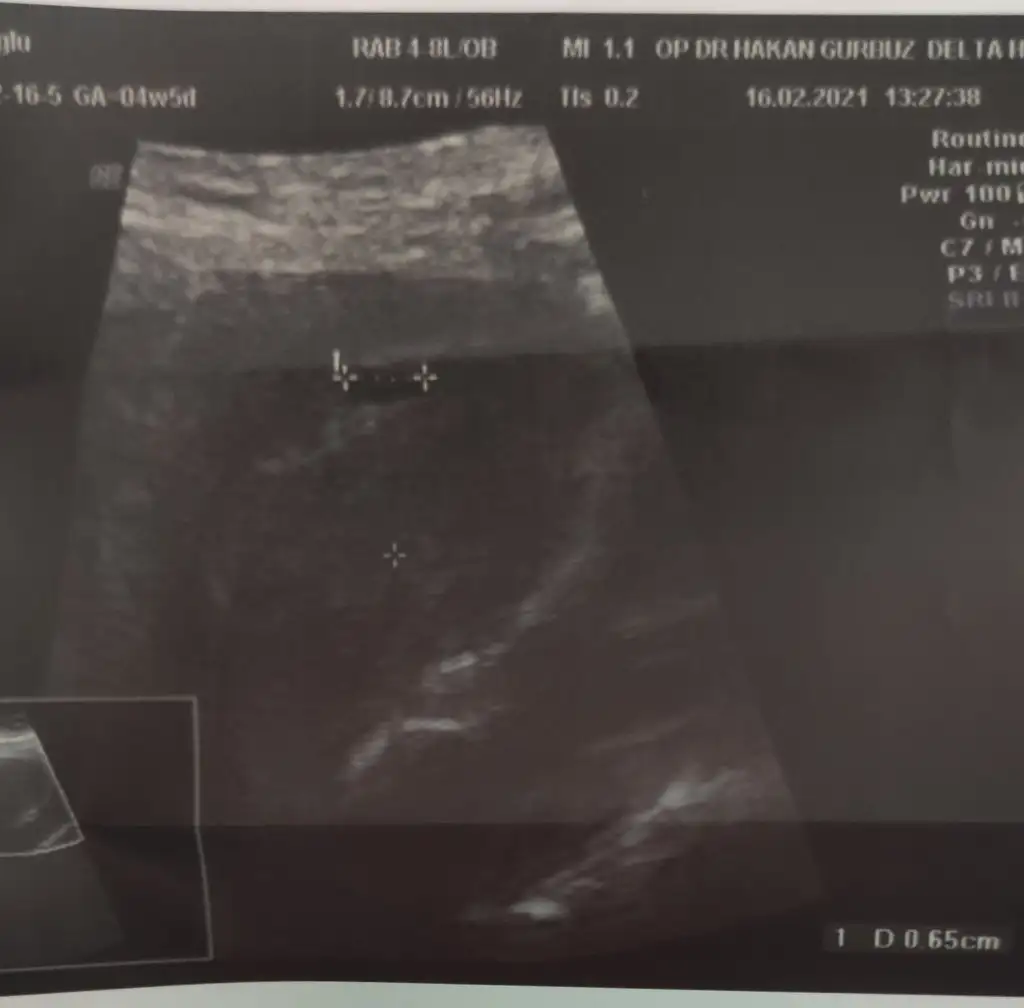

O kadarlıkken benim de görünmemişti normalBenimde dün gördük canım keseyi sat a göre dün 4+5 di...yolk saç vs görünmedi ..Ama erken dimi ?

4+5 adetine göre dedin herhalde. Crl ölçmemiş çünkü. Bide küçük ölçmüş o çentikler hiç uçtan uca değil. Dr'unu değiştir bence. Bu sefer küçük ölçer, bidahakine büyük ölçer boş yere kafa karışıklığıÖyle dimi bende onu araştırıyorum acaba neden görünmedi diyeBende 25inde gidicem.Tam 6 haftalık olucak o zaman inşallah görünür kalp atımı

Kız bende attım kese fotosunu görebilirsensayet yorumlarmisin?4+5 adetine göre dedin herhalde. Crl ölçmemiş çünkü. Bide küçük ölçmüş o çentikler hiç uçtan uca değil. Dr'unu değiştir bence. Bu sefer küçük ölçer, bidahakine büyük ölçer boş yere kafa karışıklığıBenim ilk gittiğim de büyük ölçmüştü. Yani öyle ölçmek için kör olmak lazımdı

Kese 4 mm yakın ölçmüş ama ben ölçüm çentiğini göremedim canım. Kesenin etrafı iyi kalınlaşmış aslında. Günü için de 5+1 demiş ama kese 4 mm iken 5+1 olamaz. Onu nasıl hesaplamış cihaz anlamadımBilmiyorum ki canım kaç olmadı gerektiğini Dr bı kızardı bozardi zaten bende birşey soramadım yarın tekrar gel dedi

Kese 4mm iken kaç haftalık olur 4mu evet çentikli değil ne biliyom nasıl ölçtü kesenin etrafının iyi kalınlaşması nedir ben zaten hiç birşey anlamadım keseyi gorecem diye zaten aleti içimde bı ora bı bura gezdirdi canımda yandı saklanmış dedi anlamadim dış gebelik olabilirmi?Kese 4 mm yakın ölçmüş ama ben ölçüm çentiğini göremedim canım. Kesenin etrafı iyi kalınlaşmış aslında. Günü için de 5+1 demiş ama kese 4 mm iken 5+1 olamaz. Onu nasıl hesaplamış cihaz anlamadım![]()

Yok ya ben gördüm. sağda yukarda. Yani etrafı iyi kalınlaşmış demek iyi tutunmuş. 4 mm kese tam kaçıncı güne tekabul eder bilmiyorum canım ama 5+1'den ufaktır.Kese 4mm iken kaç haftalık olur 4mu evet çentikli değil ne biliyom nasıl ölçtü kesenin etrafının iyi kalınlaşması nedir ben zaten hiç birşey anlamadım keseyi gorecem diye zaten aleti içimde bı ora bı bura gezdirdi canımda yandı saklanmış dedi anlamadim dış gebelik olabilirmi?